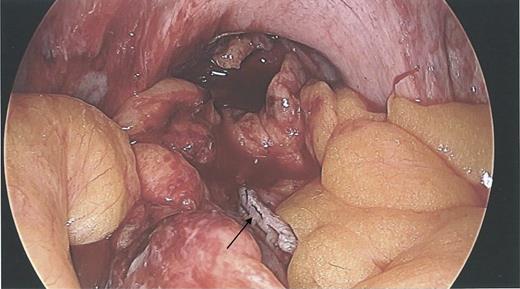

During the hysteroscopy 4 weeks later there was no evidence of an IUCD into the uterine cavity and no evidence of a perforation site in the uterus (Fig. 1). A laparoscopy followed, locating the coil threads deep in the Pouch of Douglas, with the IUCD perforating through the sigmoid colon into the lumen (Fig. 2). The IUCD was retrieved laparoscopically and the defect in the sigmoid colon was repaired by stapling the tear (Fig. 3).

Laparoscopy showing a sigmoid colon post-repair after removal of coil.